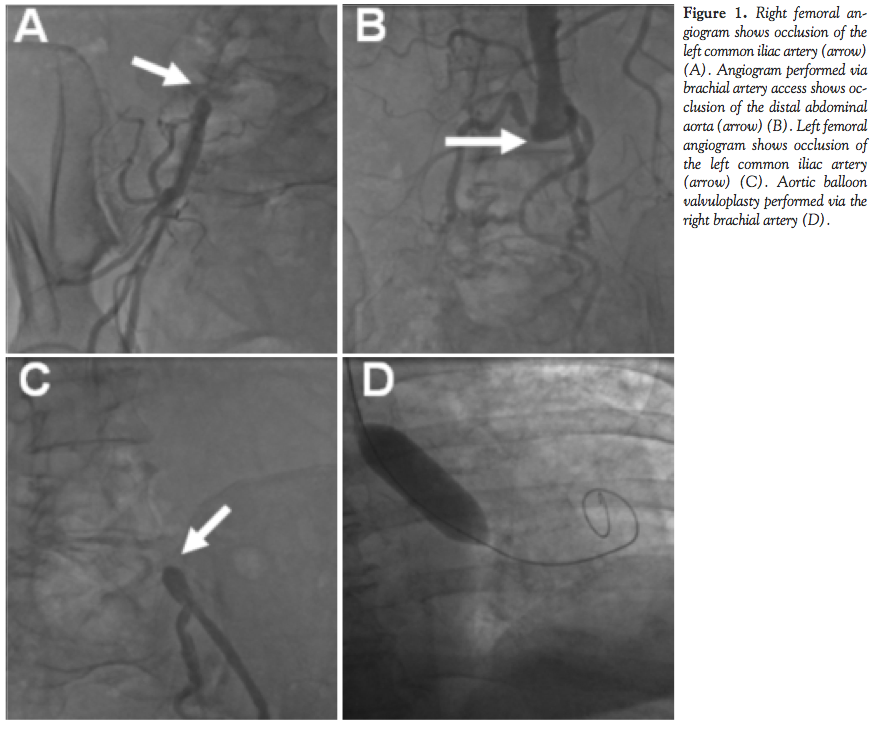

Diagnostic cardiac catheterization showed occlusion of the distal abdominal aorta, single vessel coronary artery disease with a chronic total occlusion of the mid right coronary artery, and normal left ventricular systolic function (Figure 1). The maximum and mean gradients across the aortic valve were 50 and 26 mm Hg, respectively. The aortic valve area was 0.87 cm2 and the aortic valve index was 0.37 cm2/m2. Ongoing congestive heart failure symptoms despite medical therapy mandated treatment for aortic stenosis. Access to the aorta via the femoral arteries was not deemed possible given the length of the distal aortic occlusion. Alternative access sites were considered and the brachial artery was chosen. Access to the right brachial artery was achieved using a surgical cut down approach. With blunt dissection, the right brachial artery was exposed. A small, longitudinal incision was made on the anterior surface of the artery and a .035-inch Wholey wire (Covidien) was inserted. Under direct visualization of the brachial artery, a 6 Fr sheath (Super Sheath, Boston Scientific) was inserted. Using a pigtail catheter and a 0.35-inch straight wire (Boston Scientific), the aortic valve was crossed. Simultaneous pressures within the aorta and the left ventricle were measured using a double lumen Langston catheter (Vascular Solutions Inc.). A .035-inch apex wire (Cook Medical) was advanced and coiled within the left ventricular apex. The 6 Fr sheath was removed over the apex wire. A 20 mm x 50 mm balloon (Nucleus, NuMED, Inc.) was inserted into the brachial artery under direct visualization via the arteriotomy site. With gentle retraction of the apex wire as the balloon was advanced into the brachial artery, there was no significant resistance. The balloon was placed across the aortic valve and inflated with complete balloon expansion. A second balloon inflation was performed with complete balloon expansion. Final mean and maximum gradients across the aortic valve were 20 mm Hg and 40 mm Hg, respectively. Hemostasis of the right brachial artery was achieved by direct surgical repair of the arteriotomy site. An echocardiogram the following day showed no evidence of aortic regurgitation and an aortic valve area of 1.2 cm2. The patient recovered well and was discharged from the hospital on day 3.